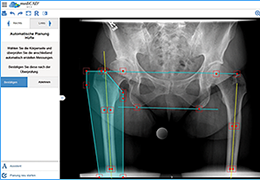

Talairach Tools

Talairach transformation is performed in two steps. The first step consists of rotating the 3D data set for each subject to be aligned with the stereotaxic axes. For this step the location of the anterior commissure (AC) and the posterior commissure (PC) as well as two rotation parameters for midsagittal alignment has to be specified interactively. In the second step the extreme points of the cerebrum are specified. These points together with the AC and PC coordinates are then used to scale the 3D data sets into the dimensions of the standard brain of the Talairach and Tournaux atlas.